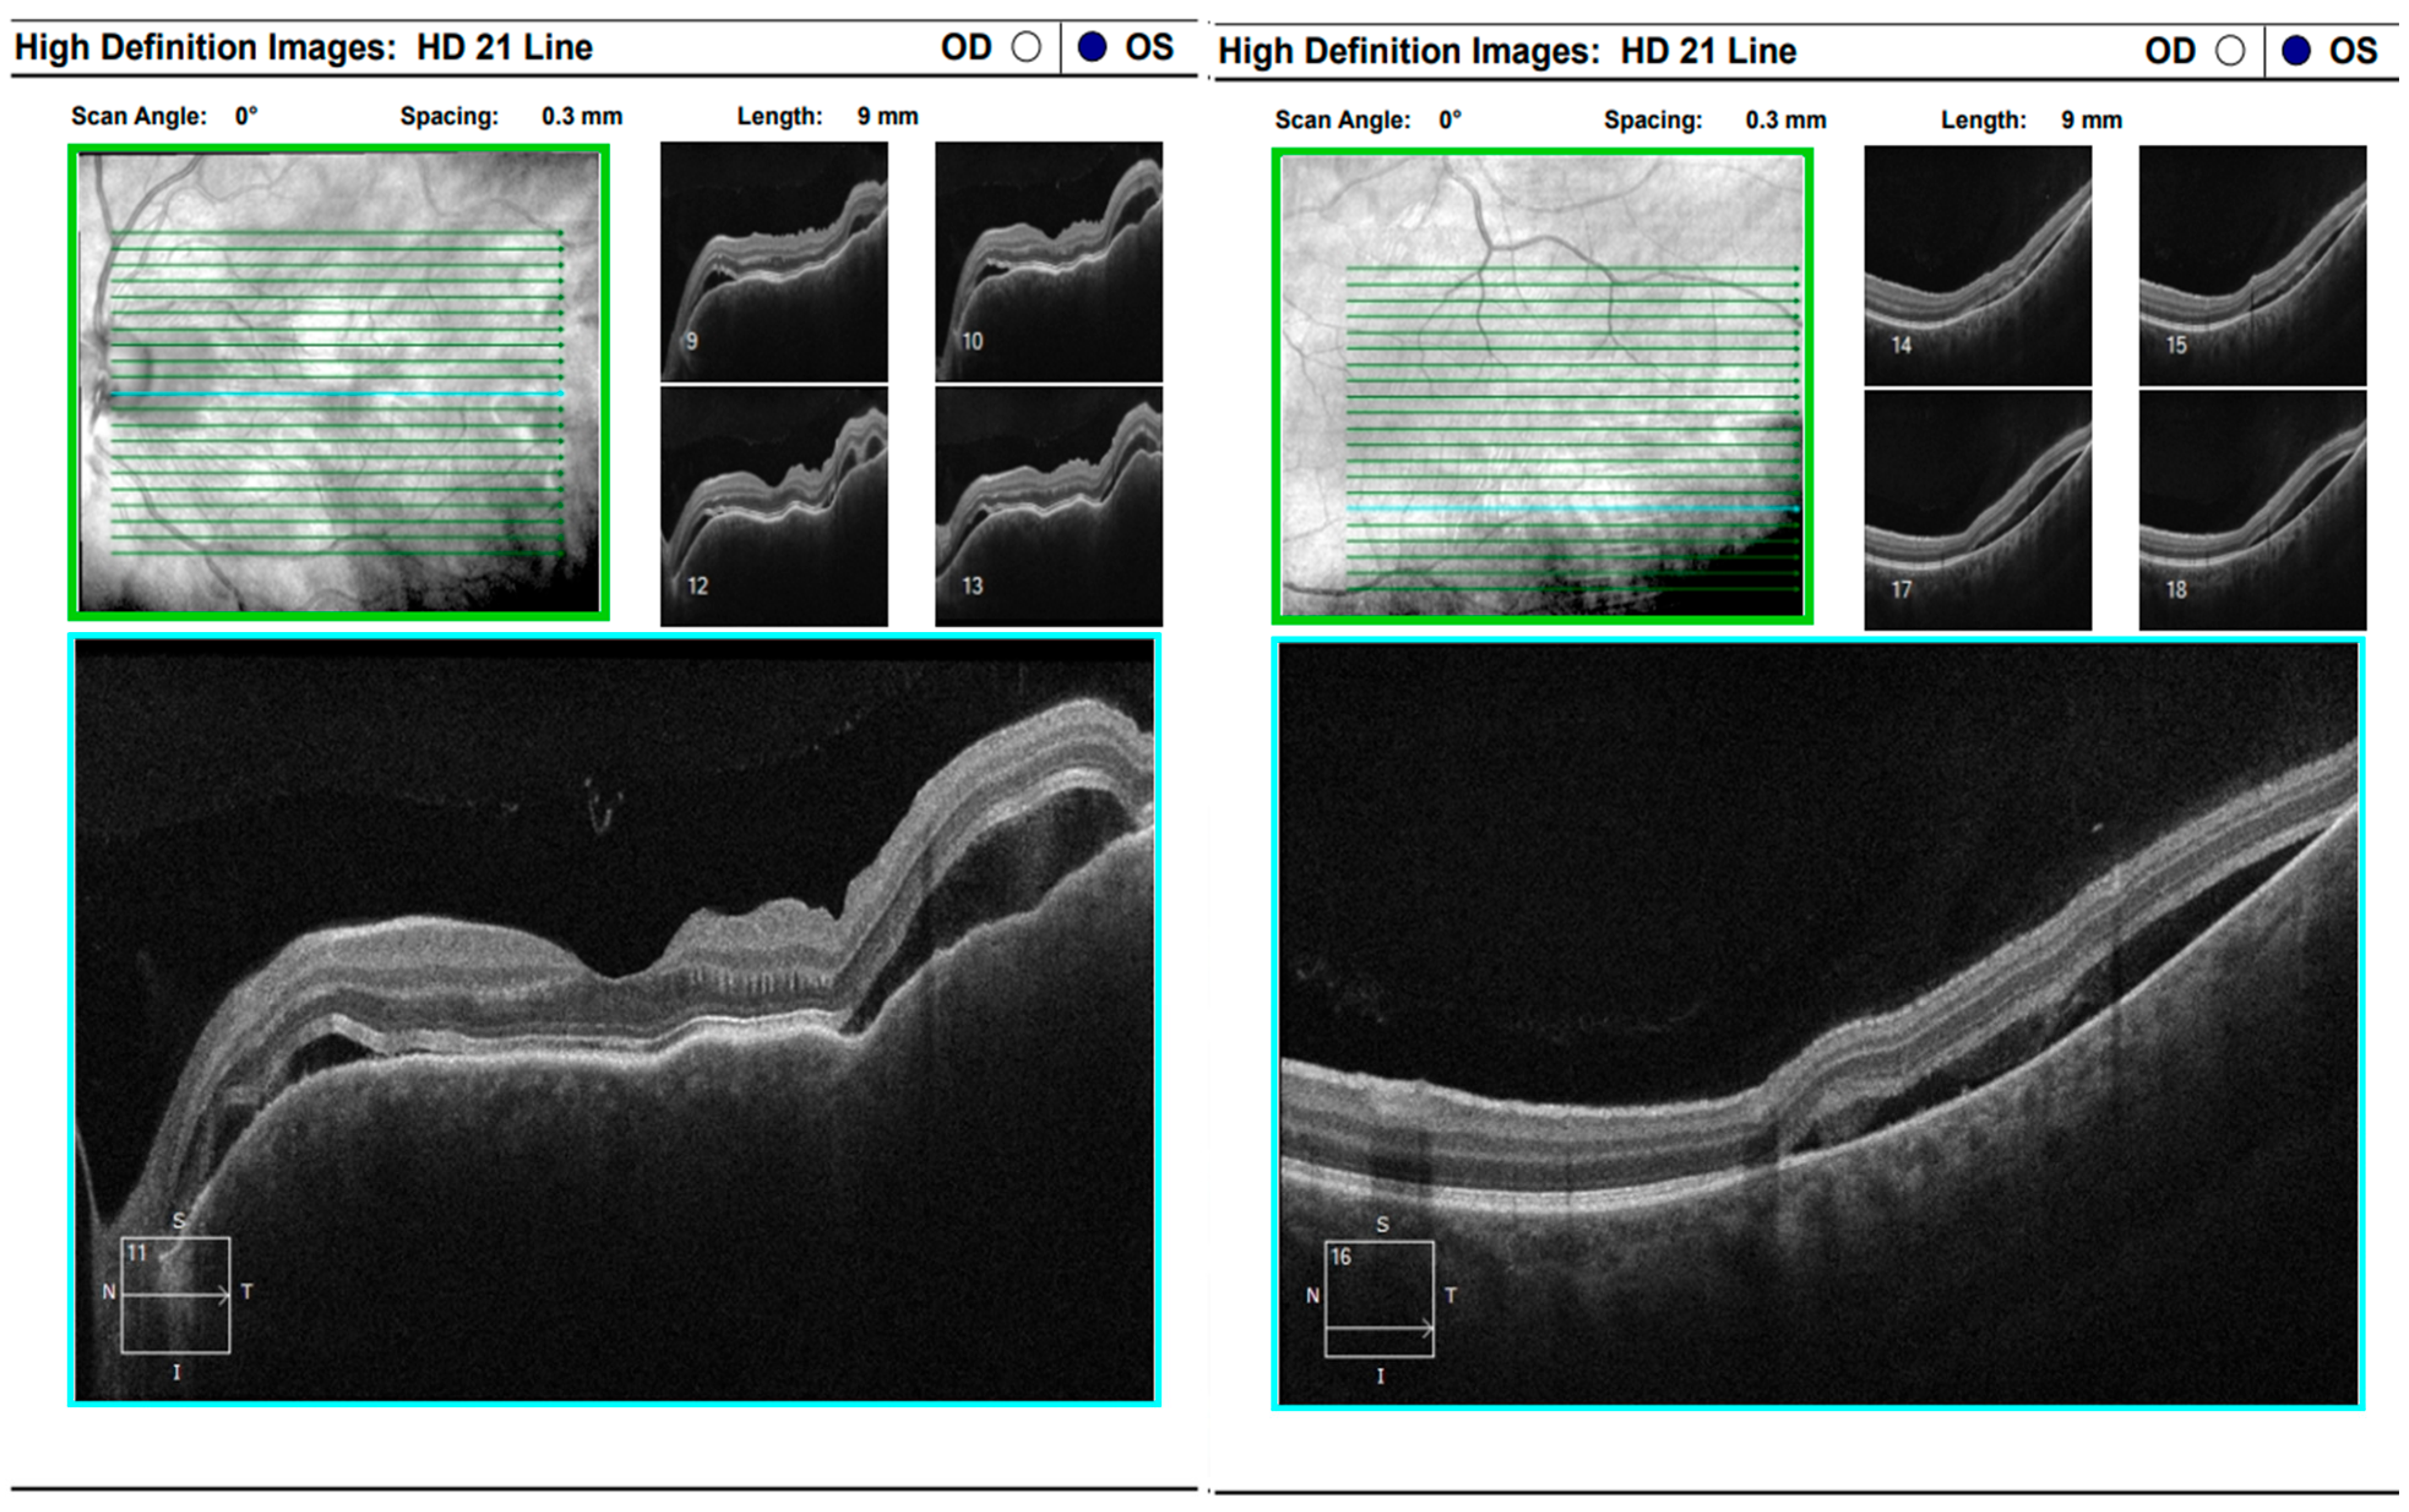

Optical coherence tomography (Zeiss Cirrus 500/5000) revealed serous fluid accumulation between the neurosensory retina and the retinal pigment epithelium, resulting in a detachment of these layers (Figure 7). In response, nonsteroidal anti-inflammatory therapy was initiated with topical Yellox drops and oral Vimovo tablets. Given the atypical presentation, a rheumatology consultation was requested, and HLA typing for B5, B27, DR1, and DR4 alleles was performed. Based on these findings, the working diagnosis was revised from primary glaucoma to a probable case of Vogt–Koyanagi–Harada syndrome.

During hospitalization, the patient received intravenous pulse therapy with Methylprednisolone. Subsequent assessment demonstrated improvement in visual acuity, with BCVA of 0.25 in the right eye and 0.15 in the left eye, while intraocular pressure was maintained between 12 and 15 mmHg. Follow-up optical coherence tomography revealed mildly blurred optic disk margins bilaterally, evidence of foveoschisis, and partial resolution of exudative retinal detachments (Figure 10). Meanwhile, results from HLA typing became available, which supported the initial suspicion of Vogt–Koyanagi–Harada syndrome.

At a follow-up visit one week later, the patient reported a decline in visual acuity and persistent headache despite initial improvement following pulse corticosteroid therapy. Examination revealed BCVA of 0.02 in the right eye and counting fingers in the left eye, with bilateral conjunctival injection, corneal edema with endothelial precipitates forming Arlt’s triangle, and a shallow anterior chamber, despite normal intraocular pressure (right eye: 9.8 mmHg, left eye: 12.4 mmHg). Posterior segment evaluation was limited due to corneal opacity. Optical coherence tomography demonstrated macular edema in both eyes and multiple areas of exudative retinal detachment in the mid-periphery (Figure 11). Following multidisciplinary discussion and comprehensive data review, a decision was made to initiate systemic immunosuppressive therapy.

Figure 7. OCT “HD 21 Line” analysis of both eyes showing serous retinal detachment.

Figure 10. Analysis protocol “Macular cube 512 × 128” of the right and left eye.

Figure 11. Analysis protocol “Macular cube 512 × 128” of the right and left eye.

Figure 12. Analysis protocol “Macular cube 512 × 128” of the right and left eye—43 days after the start of immunosuppressive therapy with reverse resorption of edema in both eyes.